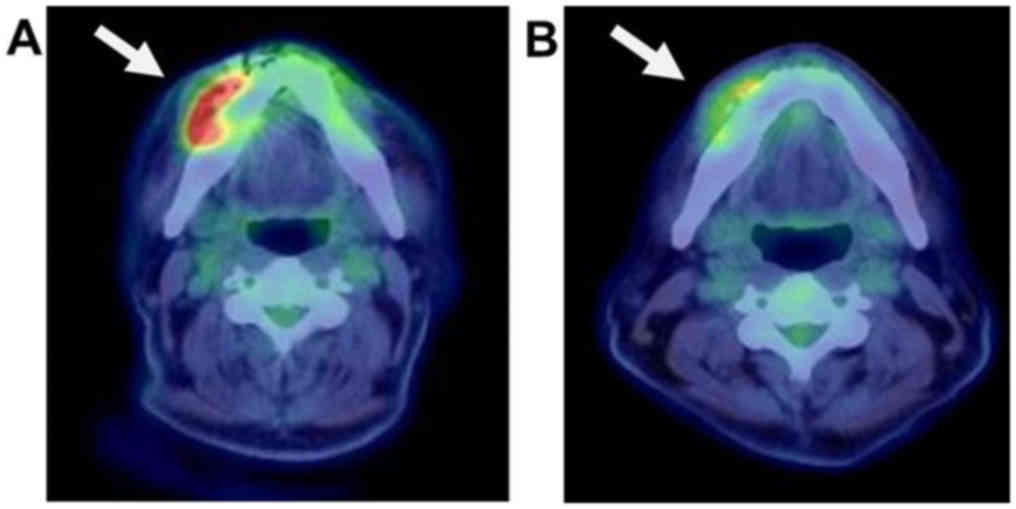

tests. Next, FDG-PET/CT and bone scintigraphy were evaluated to

identify the OS staging and any other potential lesions in the

whole body. FDG-PET showed increased FDG uptake in the surface of

right mandible [maximum standardized uptake value (SUVmax)=8.82]

(Fig. 3A). In contrast, no other FDG

uptake was seen in the whole body. Bone scintigraphy showed

abnormal bone intake on the mandibular surface, but no other sign

No preoperative radiotherapy was performed. Second, FDG-PET/CT was

performed to evaluate the effect of chemotherapy, and the mass of

the lower jaw shrank clinically and radiologically. The FDG uptake

in the right mandible was decreased (SUVmax=5.66) (Fig. 3B). No other indications of lesions

were detected in the whole body. Thrombocytopenia, resulting from

Eight months after the surgery for OS, the patient

CT scan). Follow-up third FDG-PET/CT was performed 11 months

postoperatively, and abnormal uptake was detected in the rectum

(SUVmax=14.58) (Fig. 5); on the other

hand, no other lesion identified by uptake was found in the whole

body, including the jaw, neck, bone, or lung. A colorectal tumor